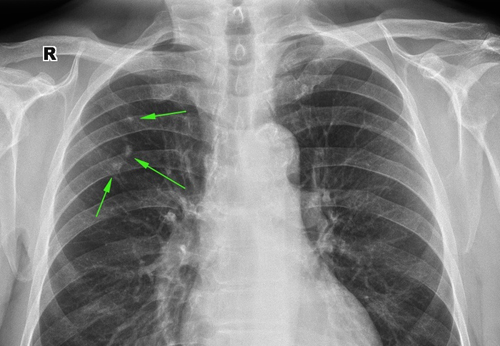

Согласно статистике, туберкулез правого легкого встречается чаще, что связано с анатомическими и физиологическими особенностями органа дыхания: правое легкое более короткое и широкое, главный бронх длиннее и делится на три ветви. Наличие трех долей в правом легком подчеркивает его важность для дыхания и газообмена, что делает его более уязвимым к инфекциям.

- Лучевые методы — рентгенография и томография являются основными при диагностике. Легкие пациентов с туберкулезом демонстрируют наличие очаговых, деструктивных и инфильтративных изменений, плевральный выпот и асимметричное увеличение корней. Очаги могут находиться не только в верхней доле (классический случай), но также затрагивать среднюю и нижнюю доли легкого. Подострая диссеминация проявляется множественными двусторонними очагами, которые чаще всего располагаются в верхних отделах и имеют тенденцию к слиянию. Эти очаги обычно сопровождаются перифокальной инфильтрацией. Однако рентгенологические признаки могут быть неспецифичными: при длительном течении туберкулеза могут развиваться пневмофиброз, бронхоэктазы и эмфизема, что усложняет диагностику. Наличие остаточных изменений в виде кальцинированных очагов может указывать на перенесенный туберкулез, и в таких случаях пациента направляют на более детальное обследование — компьютерную томографию.